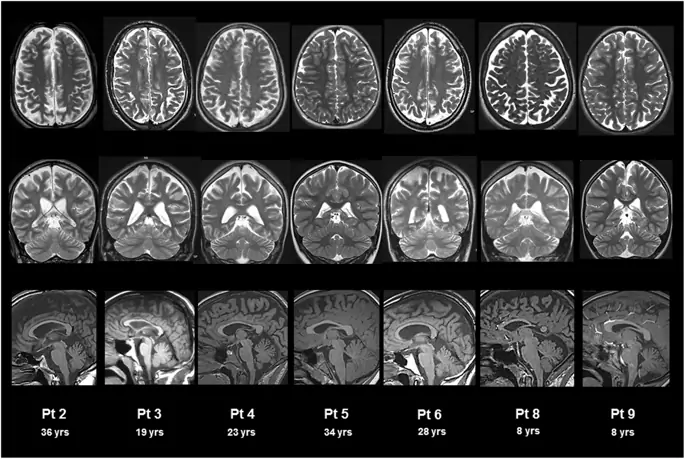

Оценки включали 14 МРТ головного и 7 спинного мозга. Все пациенты прошли как минимум одну МРТ головного мозга. Нейрорадиологические данные мозга при последующем наблюдении показаны на рис. 2. Атрофические изменения были обнаружены в супратенториальных и / или субтенториальных областях у 7/9 пациентов. Как показано в Таблице 4, атрофия включала супратенториальное белое вещество у 6/9 пациентов, легкое у 2 и умеренное у 4. Что касается субтенториальных областей, у 6/9 пациентов наблюдались умеренные атрофические изменения червя мозжечка. Нарушения мозолистого тела были обнаружены у 5/9 пациентов с легкой атрофией у 3 и умеренной у 2. У четырех из 9 пациентов (# 2, 4, 5, 6) было проведено два или более МРТ головного мозга (средний возраст в начале исследования 19, 4 ± 10, 0 лет). средний интервал между первой и последней оценкой 8, 7 ± 2, 9 года) у двух пациентов (№ 2 и 5) с годами наблюдается тенденция к ухудшению.

фигура 2

МРТ головного мозга у пациентов с синдромом ХГЧ. МРТ головного мозга, взвешенная по T2, осевая (верхняя панель), корональная (средняя панель), и взвешенная по сагиттальной (нижняя панель) T1. Атрофия различной степени выявляется в надтенториальной области (умеренная у пациентов № 2, 3, 5 и 6; легкая у пациента № 4; отсутствует у пациентов № 8 и 9), мозолистого тела (умеренная у пациентов № 3 и 5).; легкая у пациентов № 2, 4 и 6; отсутствует у пациентов № 8 и 9) и мозжечок (легкая у пациентов № 2, 4, 5, 6 и 9, отсутствует у пациентов № 3 и 8)

Изображение в полном размере

Нейрорадиологические данные также подтверждают медленное прогрессирование заболевания. Атрофия в первую очередь затрагивает субкортикальное белое вещество и, в наиболее тяжелых случаях, также слегка затрагивает корковое серое вещество, тогда как мозжечок менее поражен. Эти данные соответствуют литературным отчетам о поражениях головного мозга, наблюдаемых при нарушениях цикла мочевины, которые избирательно и в первую очередь влияют на глубокое белое вещество (30). Поскольку течение заболевания при синдроме ХГЧ обычно стабильно, с низким риском гипераммонемии после начала диеты и фармакологической терапии поражения головного мозга мягче по сравнению с другими нарушениями цикла мочевины, что представляет собой более тяжелый долгосрочный курс (31, 32). Следовательно, аномалии головного мозга, обнаруженные при синдроме HHH, вероятно, зависят не только от тяжести и продолжительности одной гипераммонемии. Фактически, 4/9 пациентов в нашей группе, которые испытывали гипераммонемическую кому, показали неоднородные результаты МРТ: № 3 и № 6 имели наиболее тяжелые клинические и нейрорадиологические результаты, в то время как № 1 и № 4 имели легкие поражения, сравнимые с таковыми у пациентов, которые никогда не испытывал тяжелой гипераммонемии.